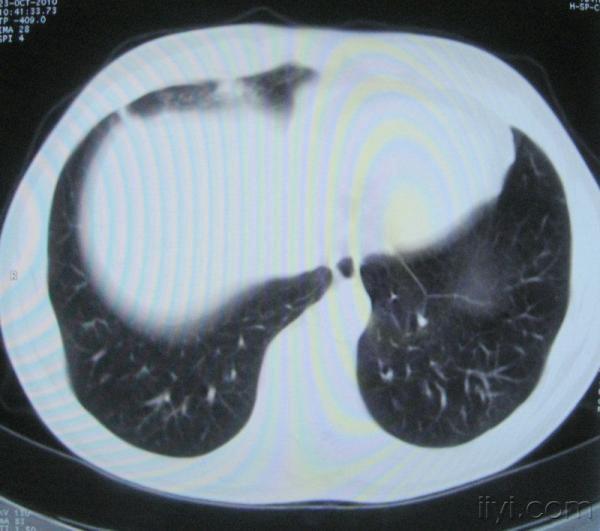

男。60岁,胸片示支气管炎治疗后复查CT。

你指那个肯定是淋巴结,中央系坏死,这很常见,特别在双侧腹股沟会经常看到。这个双侧腋窝及纵隔见多发小淋巴结征。

根据位置考虑应该是淋巴结,密度不均,是因为肿大的淋巴结中心液化坏死